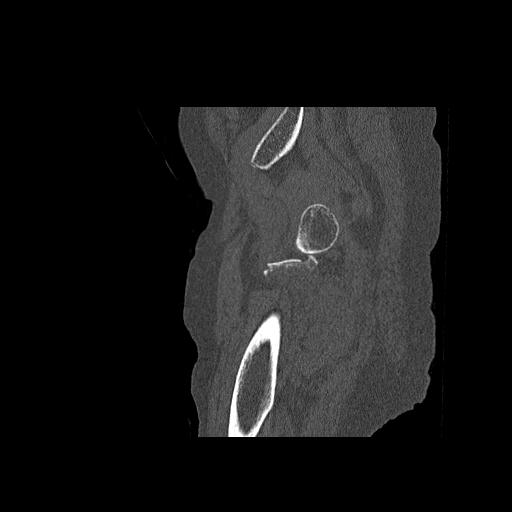

82084 1/14 1/20 股関節 2R 78歳男性 右人工骨頭